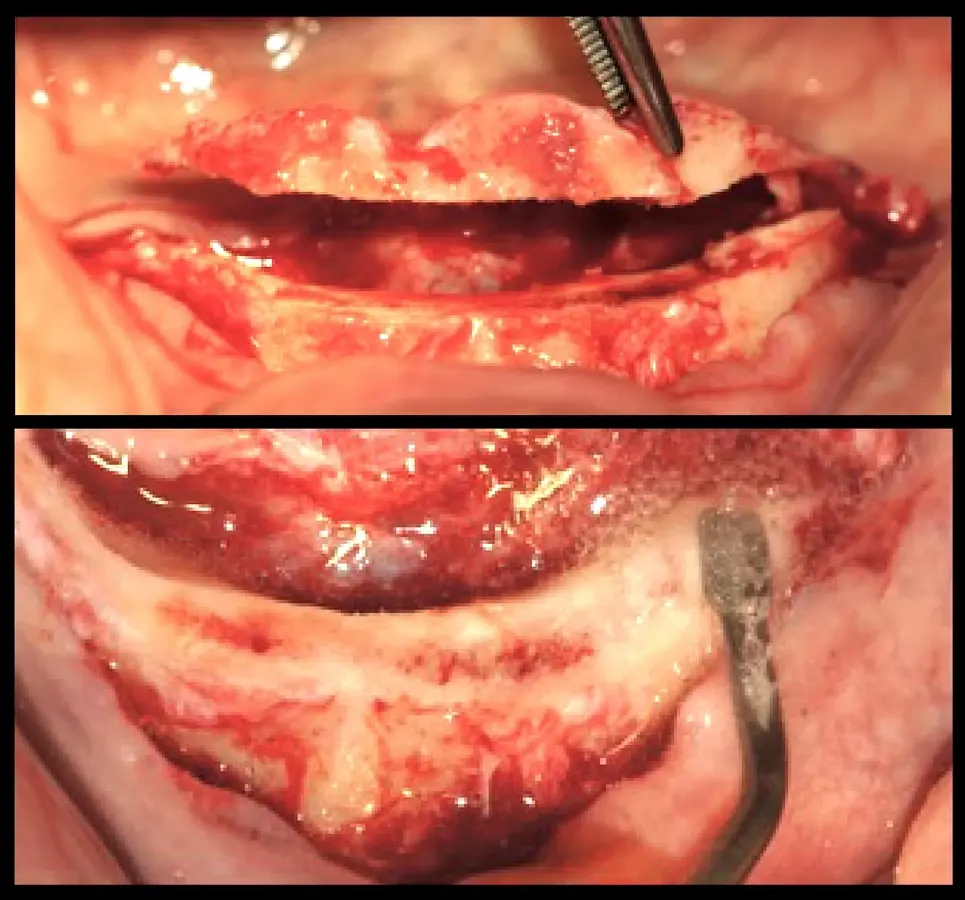

El procedimiento quirúrgico se inició con la asepsia y antisepsia del campo operatorio y del paciente. A continuación, se colocó anestesia infiltrativa a nivel de la proyección de salida de los agujeros mentonianos, se procedió con la incisión y decolado. Se realizó la delimitación y regularización del reborde óseo mediante el inserto aserrado B7 y el subsiguiente remodelado del reborde crestal mediante el inserto plano diamantado S1 del piezoeléctrico Piezomed (W&H) (Figuras 4 y 5).

Remodelado óseo

Figura 4. Remodelado óseo mínimamente traumático realizado con tecnología piezoeléctrica.